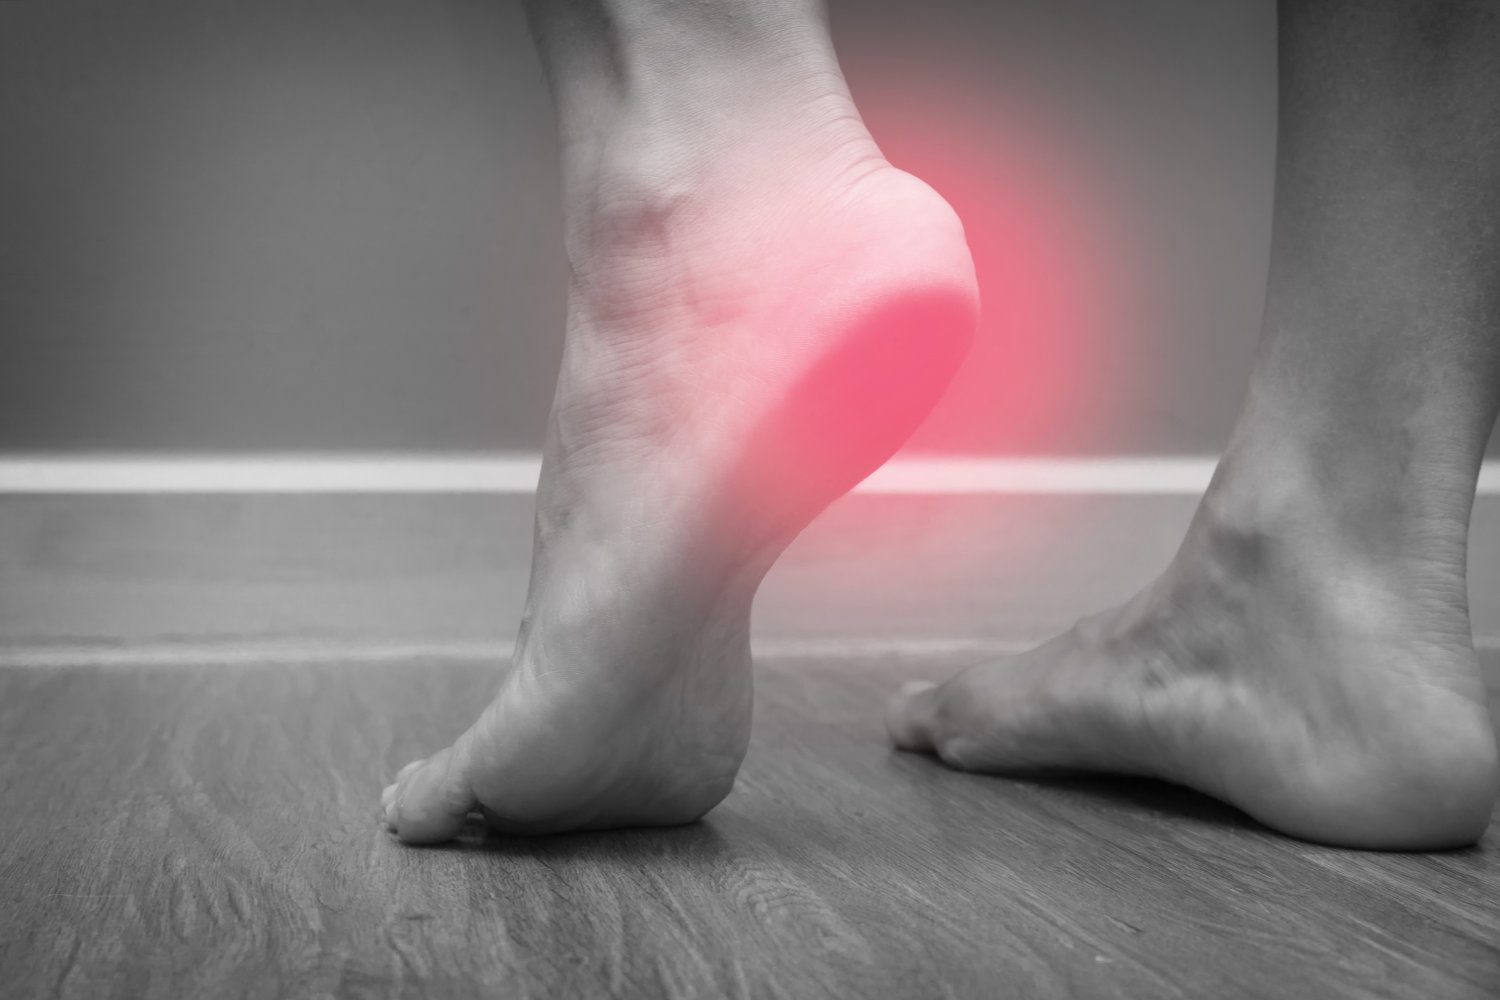

Heel Pain

Heel pain is one of the most common conditions treated by podiatrists. The most common incidence of heel ...